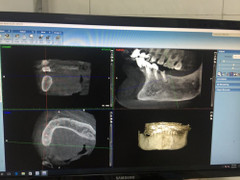

GS. TS. Trịnh Đình Hải, Giám đốc Bệnh viện Răng hàm mặt Trung ương cho biết, lần đầu tiên, các bác sĩ ngành răng hàm mặt Việt Nam đã thực hiện ca phẫu thuật, cấy ghép răng cho một cụ bà trên nền bệnh cao huyết áp.